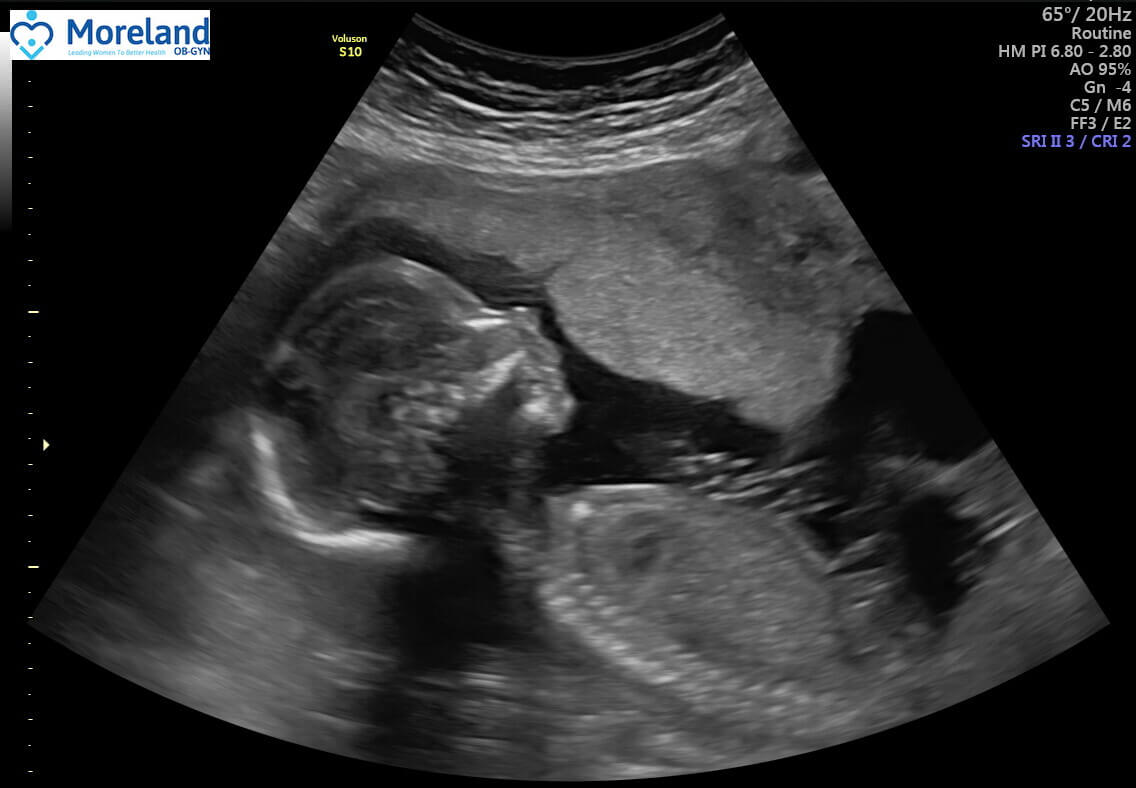

25-week ultrasound (size of Aladdin's magic lamp)

We got to see a 3D image of his beautiful little baby face! (and his umbilical cord!)